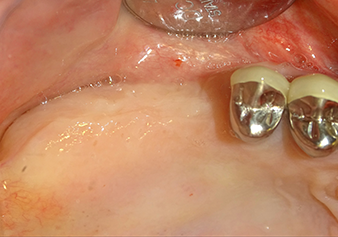

Situation préopératoire : La crête alvéolaire a bien cicatrisé et la gencive est suffisamment large et kératinisée.

Fig.1 : Situation préopératoire : La crête alvéolaire a bien cicatrisé et la gencive est suffisamment large et kératinisée.